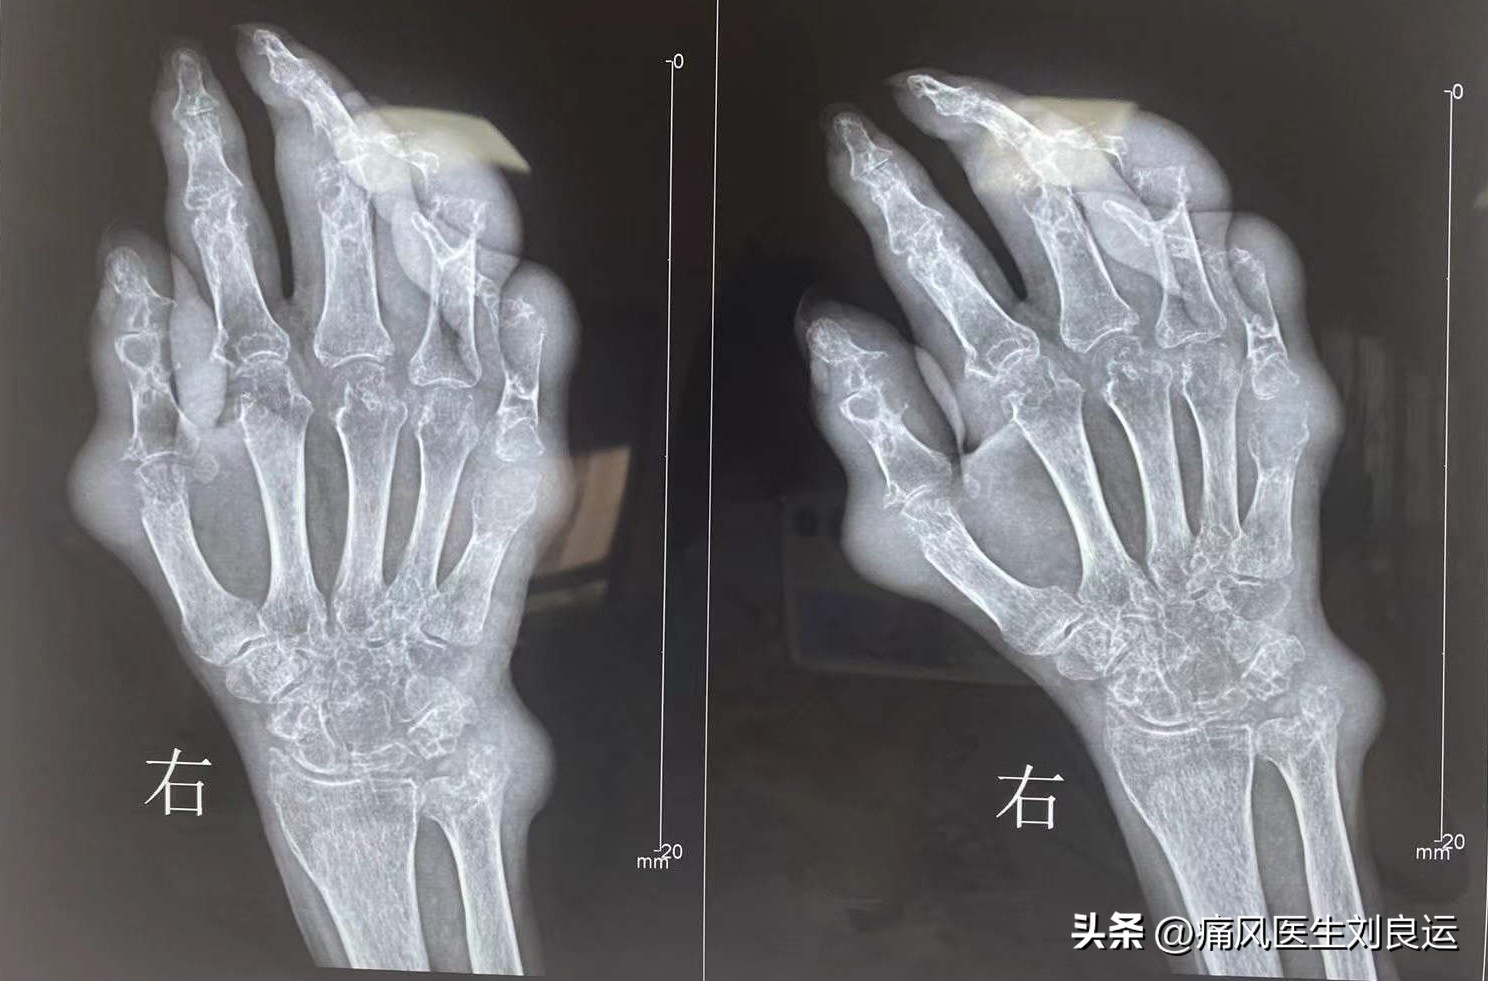

吴先生右手多关节痛风石

如今的他双手、双肘、双踝、双脚,都长出了大小不一的痛风石。尤其是右手手心和手背,更是密布了不少痛风石;而手肘痛风石更是有鹅蛋大小。

吴先生手掌多处痛风石